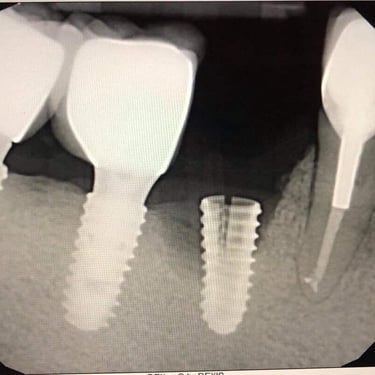

Implantes dentales fracasados

Los implantes dentales fracasados son aquellos que no se han integrado correctamente con el hueso o han desarrollado complicaciones postoperatorias.

Los pacientes pueden notar movilidad en el implante, dolor o inflamación.

El tratamiento puede incluir la extracción del implante fallido y la preparación para un nuevo implante.